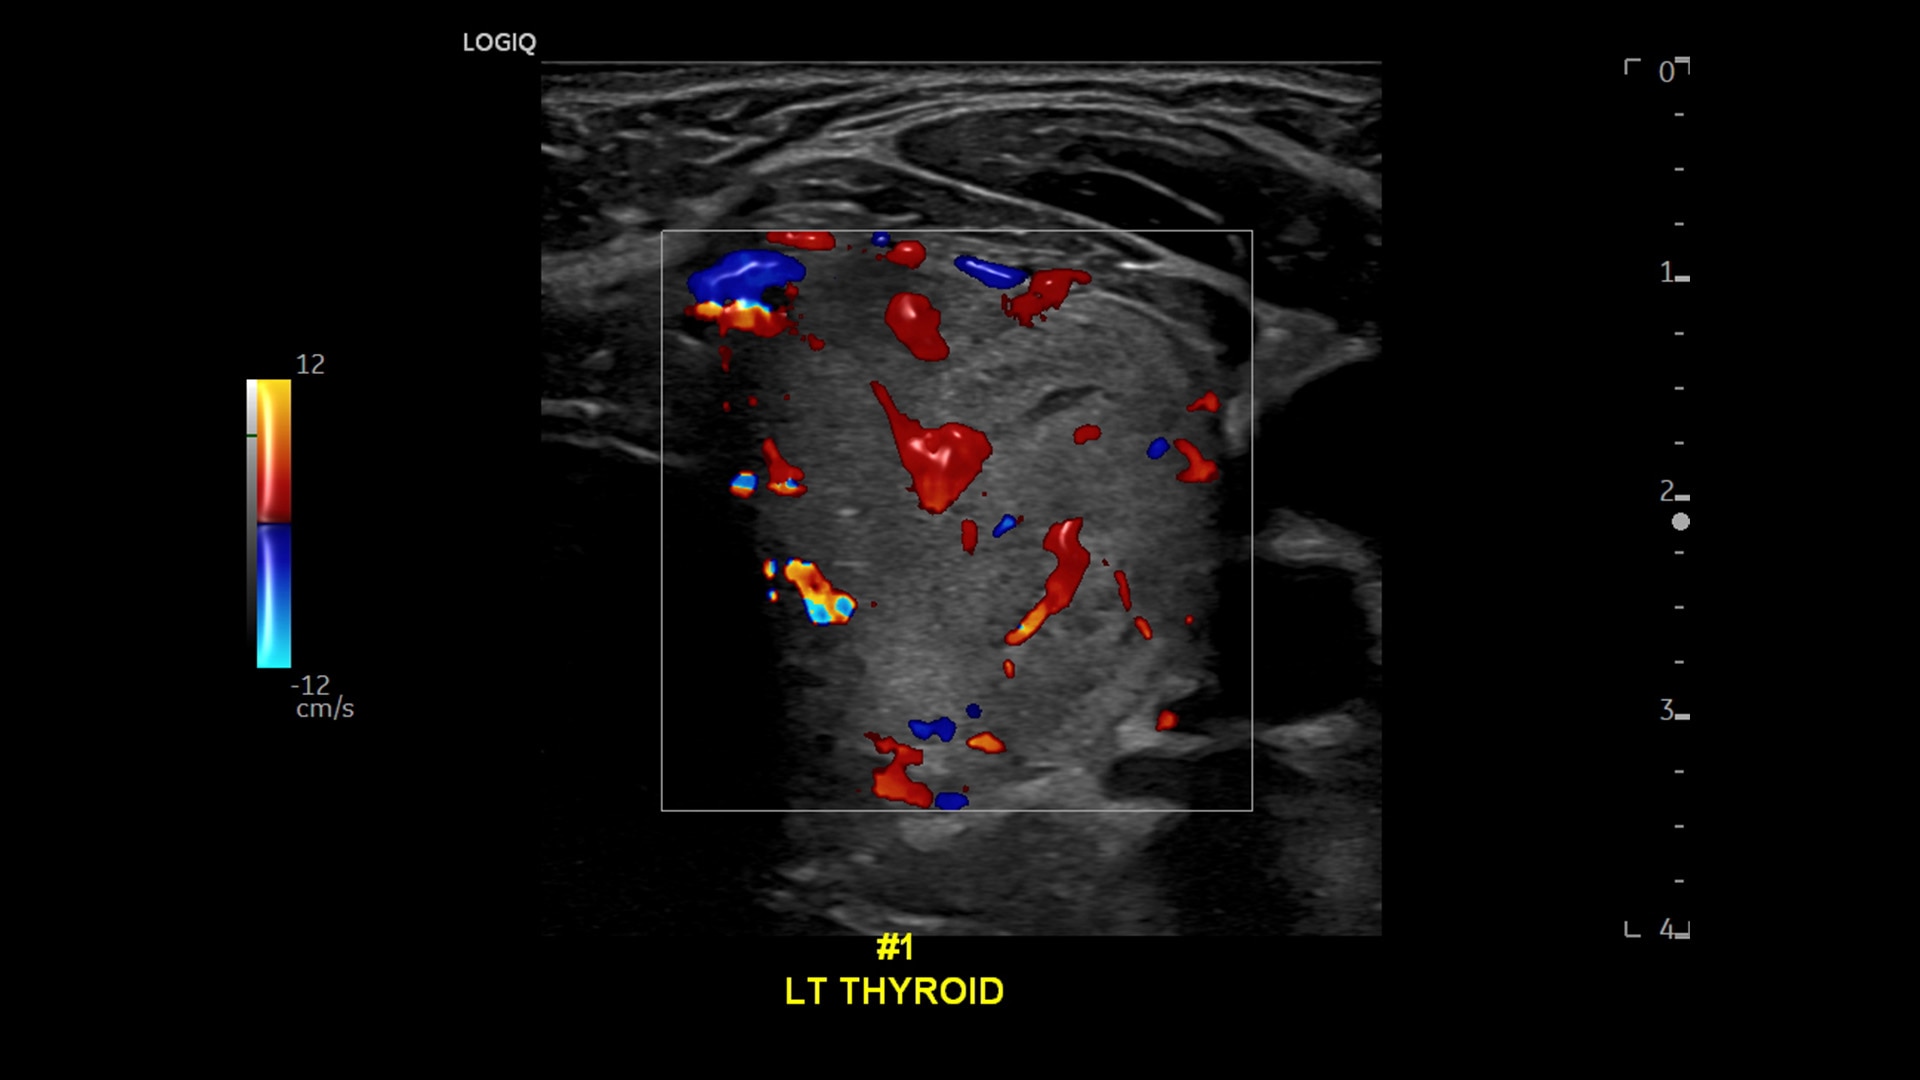

Strength and power to enhance clinical capabilities and deliver exceptional image quality